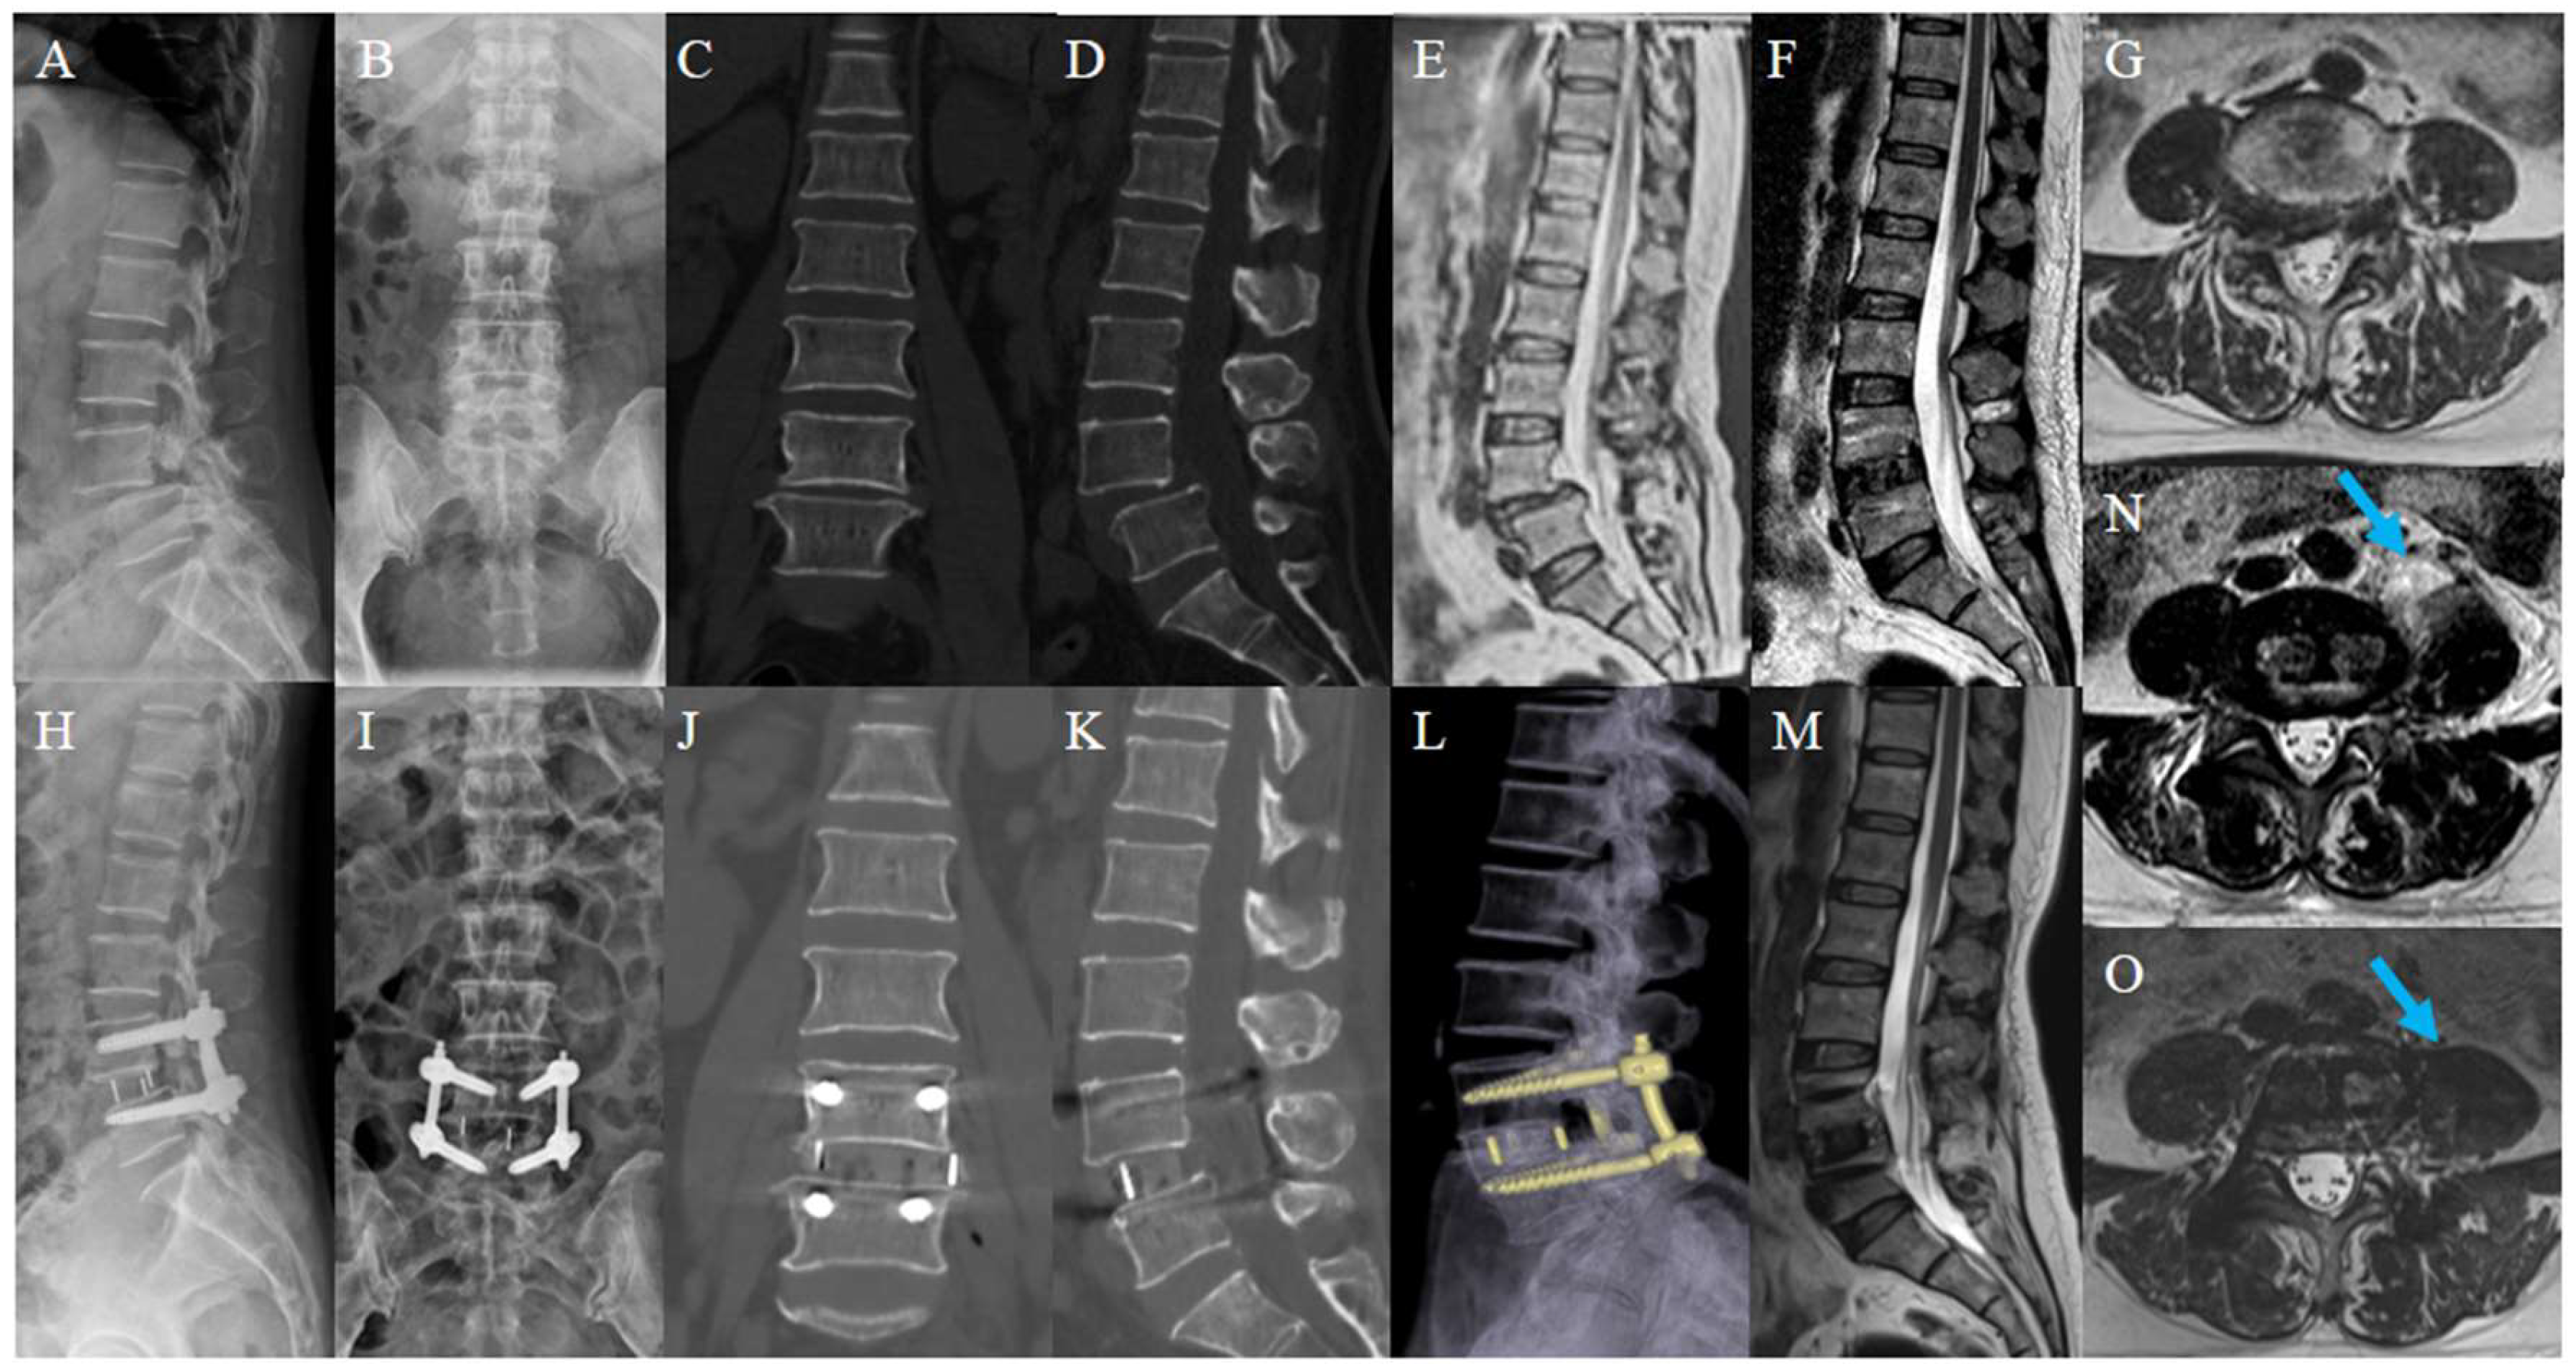

OLIF has been widely used in spine surgery because it allows back muscles and tissues to be well protected. Consistent with previous findings, our study reconfirmed that OLIF is safe and effective in the treatment of degenerative lumbar diseases [14,15,16,17,18,19]. Intervertebral space, foramen, and ligamentum flavum were distracted intraoperatively, therefore relieving neurological symptoms caused by intervertebral space collapse or foraminal stenosis and dorsal compression of the thecal sac. In addition, a larger-sized cage combined with PPSF was able to effectively relieve low-back pain caused by mechanical instability. Thus, OLIF has gained more attention with reliable clinical efficacy [20,21]. Figure 4 demonstrates a typical case with 1-year follow-up.

Figure 4.

Typical case. A 55-year-old woman, presented with pain and numbness in the right lower extremity for 5 years; her condition worsened for 3 weeks. Preoperative lumbar X-ray (A,B); preoperative lumbar CT (C,D); preoperative lumbar MRI. Preoperative images showed the L4 spondylolisthesis and stenosis at L4-5 (E,G); postoperative lumbar X-ray showed L4 was reduced (H,I); postoperative lumbar CT showed the distraction of disc height (J,K); postoperative lumbar MRI showed satisfactory decompression and a huge swelling of the left psoas major (arrow) (F,N). Lumbar CT reconstruction and MRI at 1-year follow-up showed solid fusion with no cage subsidence (L). Swelling of the left psoas major reduced significantly and its area recovered (arrow) (M,O).